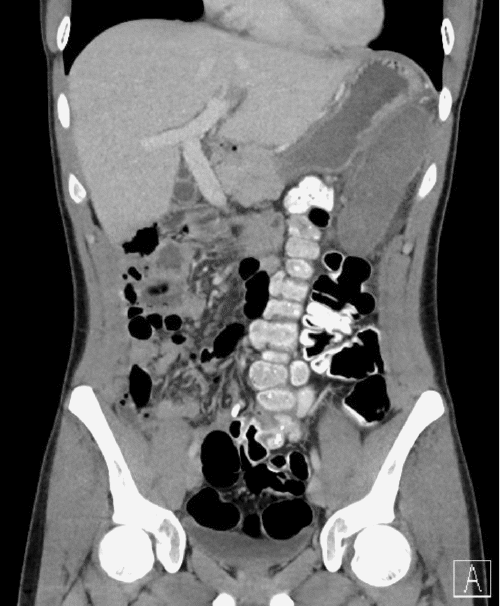

A computed tomography (CT) scan was conducted and reviewed by radiology. Based on clinical evaluation, it was determined that the patient exhibited congenital nonrotation of the intestine, with the entire colon positioned along the left abdomen and pelvis. There was no indication of an associated obstructive condition at the time of assessment (Figure 1). Additionally, evidence of polysplenia in the left upper abdomen was detected.

Figure 1. Coronal CT Scan. Published with Permission

Colon on left, small bowel on right due to congenital malrotation